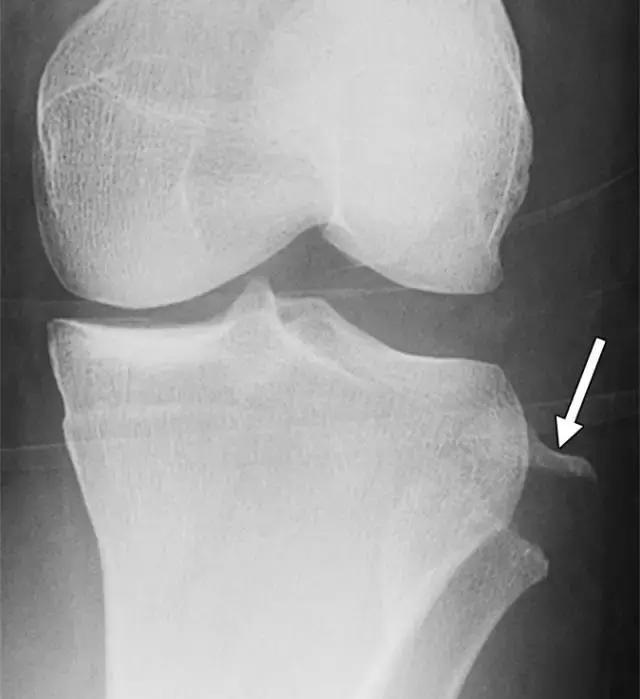

在放射照片上,Segond骨折显示为邻近近侧外侧胫骨平台的小骨片,并且在膝关节的前后放射照片上能很好的显示(图5A)。在MR图像上,由于相邻软组织中突出的异常信号强度,小的撕裂片段可能不像放射照片那样显着(图5B),但膝关节内更重要的损伤可以更好地显示。在75-100%的Segond骨折患者中发现ACL的撕裂,66-75%的病例中同时存在半月板损伤。

图5A -30岁的Segond骨折患者。A,膝关节前后位X线照片显示沿胫骨外侧平台的薄线状骨折片段(箭头)。

图5B骨折挫伤存在于股骨外侧髁上,前交叉韧带可以看到较低低信号,表明撕裂(箭头)。